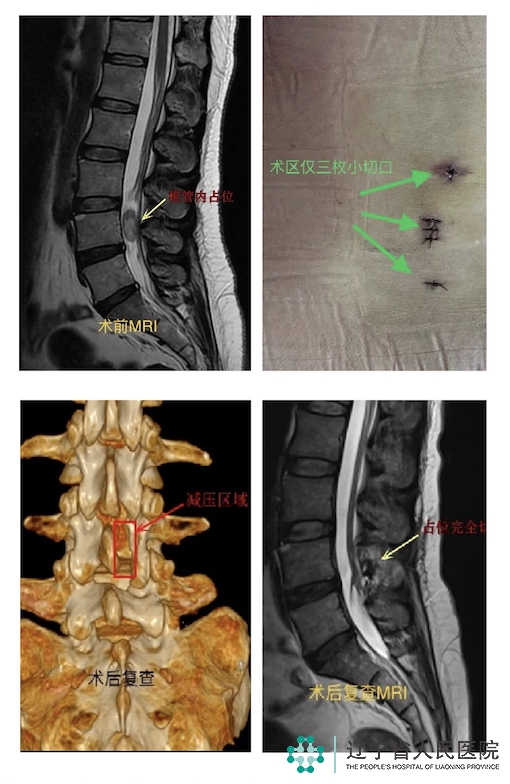

6月27日晚8时,一对神色忧虑的母女敲开了骨五科急诊室的大门,“我们从吉林白山开了一天的车赶来的,我需要做手术,能帮我联系上任伟剑(副)主任吗?”患者L4椎体水平后方硬膜内有...